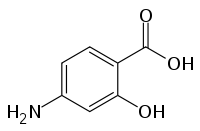

| Various pharmaceutical tuberculosis treatments and their actions | |

p-aminosalicylic acid |

PAS | P |

The second line drugs (WHO groups 2, 3 and 4) are only used to treat disease that is resistant to first line therapy (i.e., for extensively drug-resistant tuberculosis (XDR-TB) or multidrug-resistant tuberculosis (MDR-TB)).[5][6] A drug may be classed as second-line instead of first-line for one of three possible reasons: it may be less effective than the first-line drugs (e.g., p-aminosalicylic acid); or, it may have toxic side-effects (e.g., cycloserine); or it may be effective, but unavailable in many developing countries (e.g., fluoroquinolones):